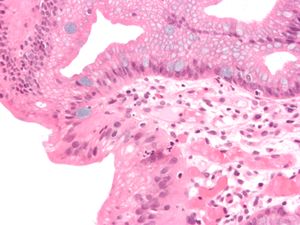

Micrograph of a gastro-esophageal junction with pancreatic acinar metaplasia. The esophageal mucosa (stratified squamous epithelium) is seen on the right. The gastric mucosa (simple columnar epithelium) is seen on the left. The metaplastic epithelial is at the junction (center of image) and has an intensely eosinophilic (bright pink) cytoplasm. H&E stain. | |